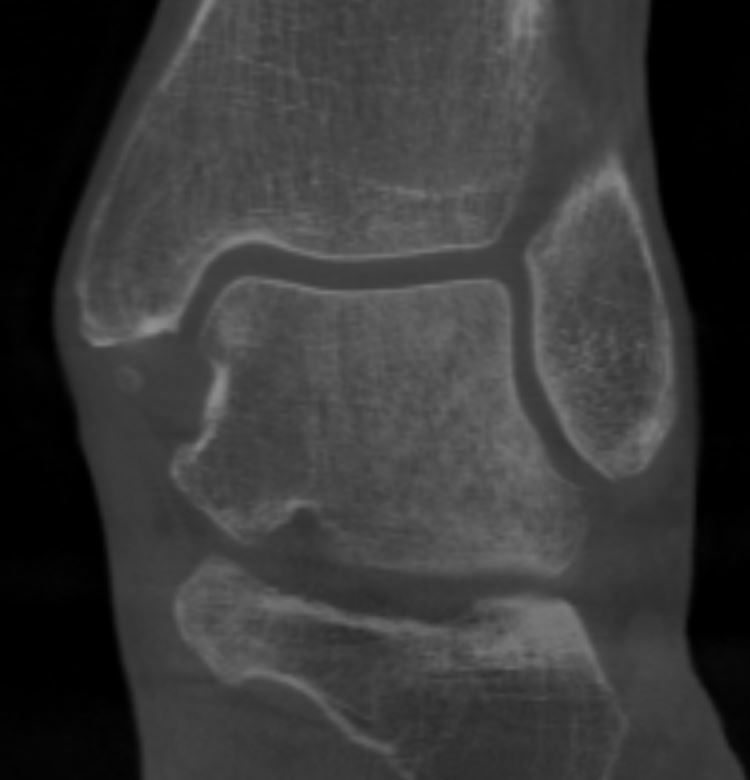

Home Schwerpunkte Krankheitsbilder Osteochondrale Läsion des Talus (OCL) – Ursachen, Symptome, MRT/DVT-Diagnostik & moderne Therapie Talus DVT frontal Zysten – OCL 2018 vor der entstehenung – aber mit verdznekltem Talus

Talus DVT frontal Zysten – OCL 2018 vor der entstehenung – aber mit verdznekltem Talus

osteochondrale Läsion talus DVT 2018 ohne beschwerden